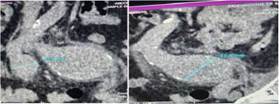

Figura 1: Tomografía simple Abdomino pélvica. La primera imagen nos muestra la arteria iliaca derecha y la segunda la arteria iliaca izquierda. Autoría propia

Se presenta el caso de un paciente masculino de 75 años de edad, que acude al servicio de emergencias del Hospital obrero N°2 de la Caja nacional de Salud, Cochabamba, con un cuadro clínico de más o menos 3 semanas de evolución, caracterizado por presentar dolor lumbar de inicio súbito, secundario a realizar esfuerzos grandes, debilidad en miembros inferiores, astenia, adinamia y mareos. Antecedentes: Insuficiencia cardiaca, enfermedad de Chagas, bloqueo auriculoventricular grado 3 y portador de marcapasos hace 20 años. Al examen físico regular estado general, consciente, orientado, afebril, hemodinámicamente estable, al examen físico regional sin particularidades. Laboratorios dentro de parámetros normales. Se le realiza exámenes complementarios: Ecografía abdominal que reporta un aneurisma fusiforme de la arteria iliaca común izquierda, trombosis mural aneurismática de evolución subaguda, que compromete el 50% de la luz aproximadamente y una tomografía Abdominal con contraste donde se evidencia aneurisma bi-iliaco, con diámetros de arteria iliaca izquierda (64 mm) y derecha (35 mm), que se extiende la bifurcación de la iliaca sin datos de disección ni sangrado. Paciente es transferido al servicio de Cirugía, donde se le propone cirugía y el paciente acepta. Se le realiza como tratamiento quirúrgico una derivación aorto-bifemoral con una prótesis de dacrón, por un abordaje transabdominal. Pasa a salas de terapia intensiva, donde como tratamiento médico se le da soporte con fluidoterapia, analgésicos, profilaxis antibiótica y anticoagulación, evolucionando favorablemente. El décimo segundo día postoperatorio se realiza ecografía de control, donde se evidencia permeabilidad de la prótesis, pasando a salas generales. Es dado de alta el décimo quinto día postoperatorio.